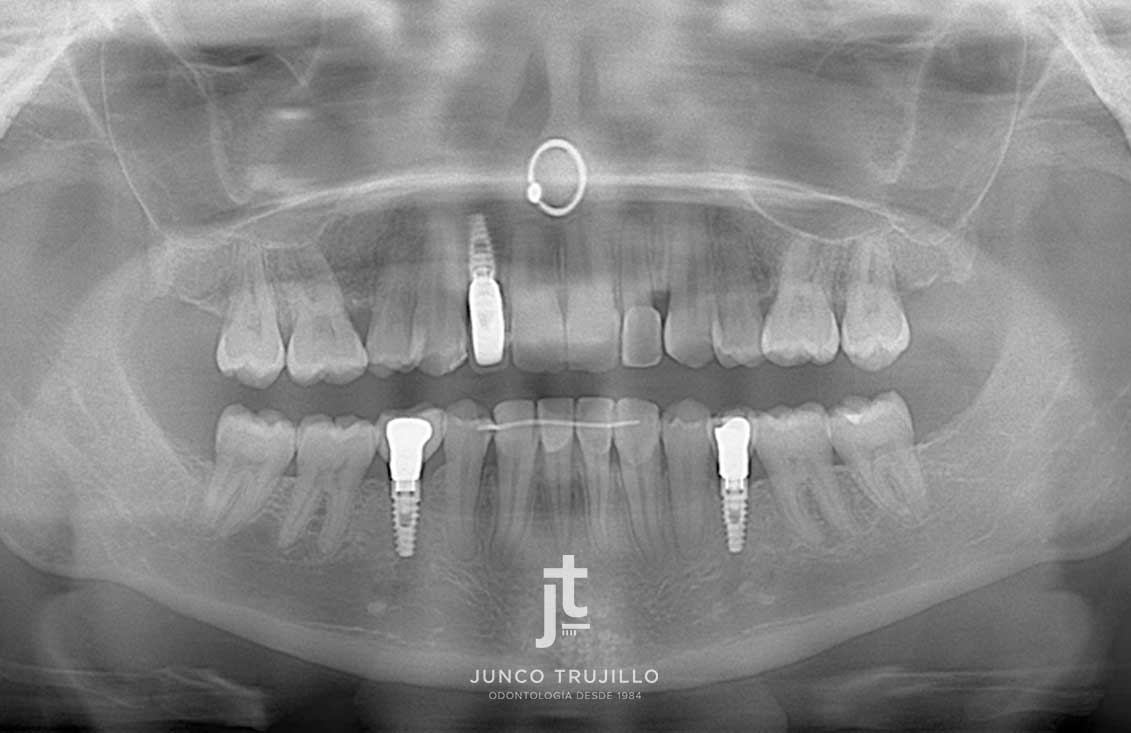

En nuestra clínica realizamos un estudio personalizado con radiografías y escáner 3D para planificar cada tratamiento con precisión. Los Implantes en Palencia permiten recuperar la capacidad de masticar con normalidad, mejorar la pronunciación y evitar la pérdida ósea que se produce tras la ausencia dental. Además, ayudan a mantener la armonía facial y la salud del resto de piezas dentales, evitando que se desplacen.

Casos de implantes